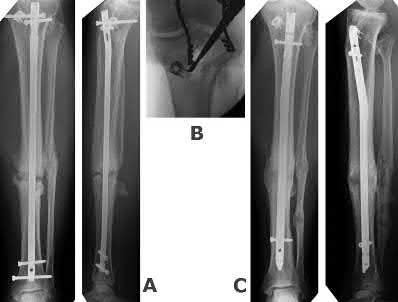

ORTHOPEDIC MCQS ONLINE OB 20 TRAUMA 2A OrthoCash 2020 A 25 year-old-male presents with the injury seen in Fi…

ORTHOPEDIC MCQS ONLINE OB 20 TRAUMA 2B CT angiography and admit the patient for hourly neurovascular checks …